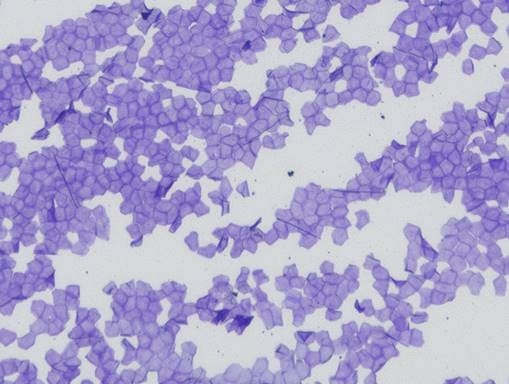

■乳幼児の角層構造の顕微鏡写真(成人との比較)

乳幼児(頬部)

乳幼児(頬部)全体的に細胞が小さく、細胞同士の接着力が弱いため、バリア機能が未熟。